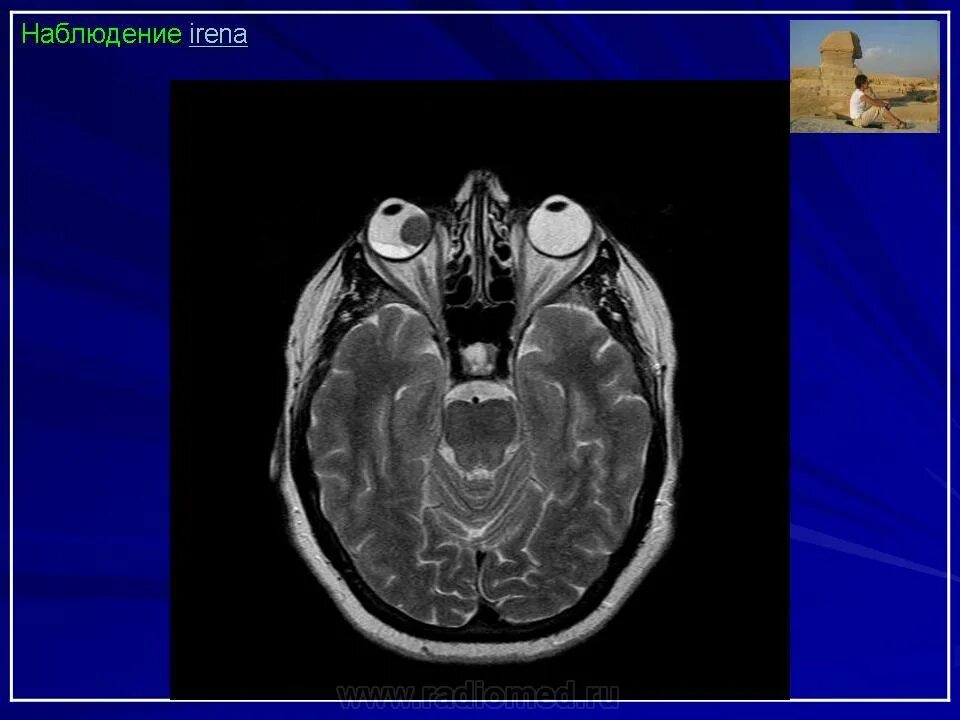

Данные кт